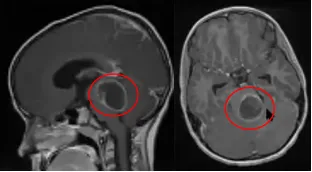

小帕被确诊的时候,肿瘤已经相当大了——他的家人用"像鸡蛋一样"来形容。最初让家人察觉异常的,是他反复出现的头痛,以及越来越明显的眼球运动障碍:眼球无法向上转动,瞳孔对光反应迟钝但调节反射还在,集合时眼球出现异常震颤。这组症状有一个专有名称,叫帕里诺综合征,是中脑背侧受压后的典型表现,说明肿瘤已经对这一区域产生了实质性影响。

帕里诺综合征:由中脑背侧病变引起,核心表现为双眼上视麻痹、光-近反射分离(对光反应消失但调节反射保留)、集合-回缩性眼震及眼睑退缩,由法国眼科医生Henri Parinaud于19世纪末首次描述。

本地医生的意见是保守观察——毕竟这类肿瘤生长缓慢,手术风险也不可忽视。但鲁特卡教授在详细了解小帕的病史和影像资料后,给出了不同的判断:孩子已经有明确的手术指征,现在可以手术。

小帕的母亲最终选择了手术。手术顺利完成,肿瘤被全切。术后一年,复查无复发,手术前困扰小帕的帕里诺综合征也已消失。